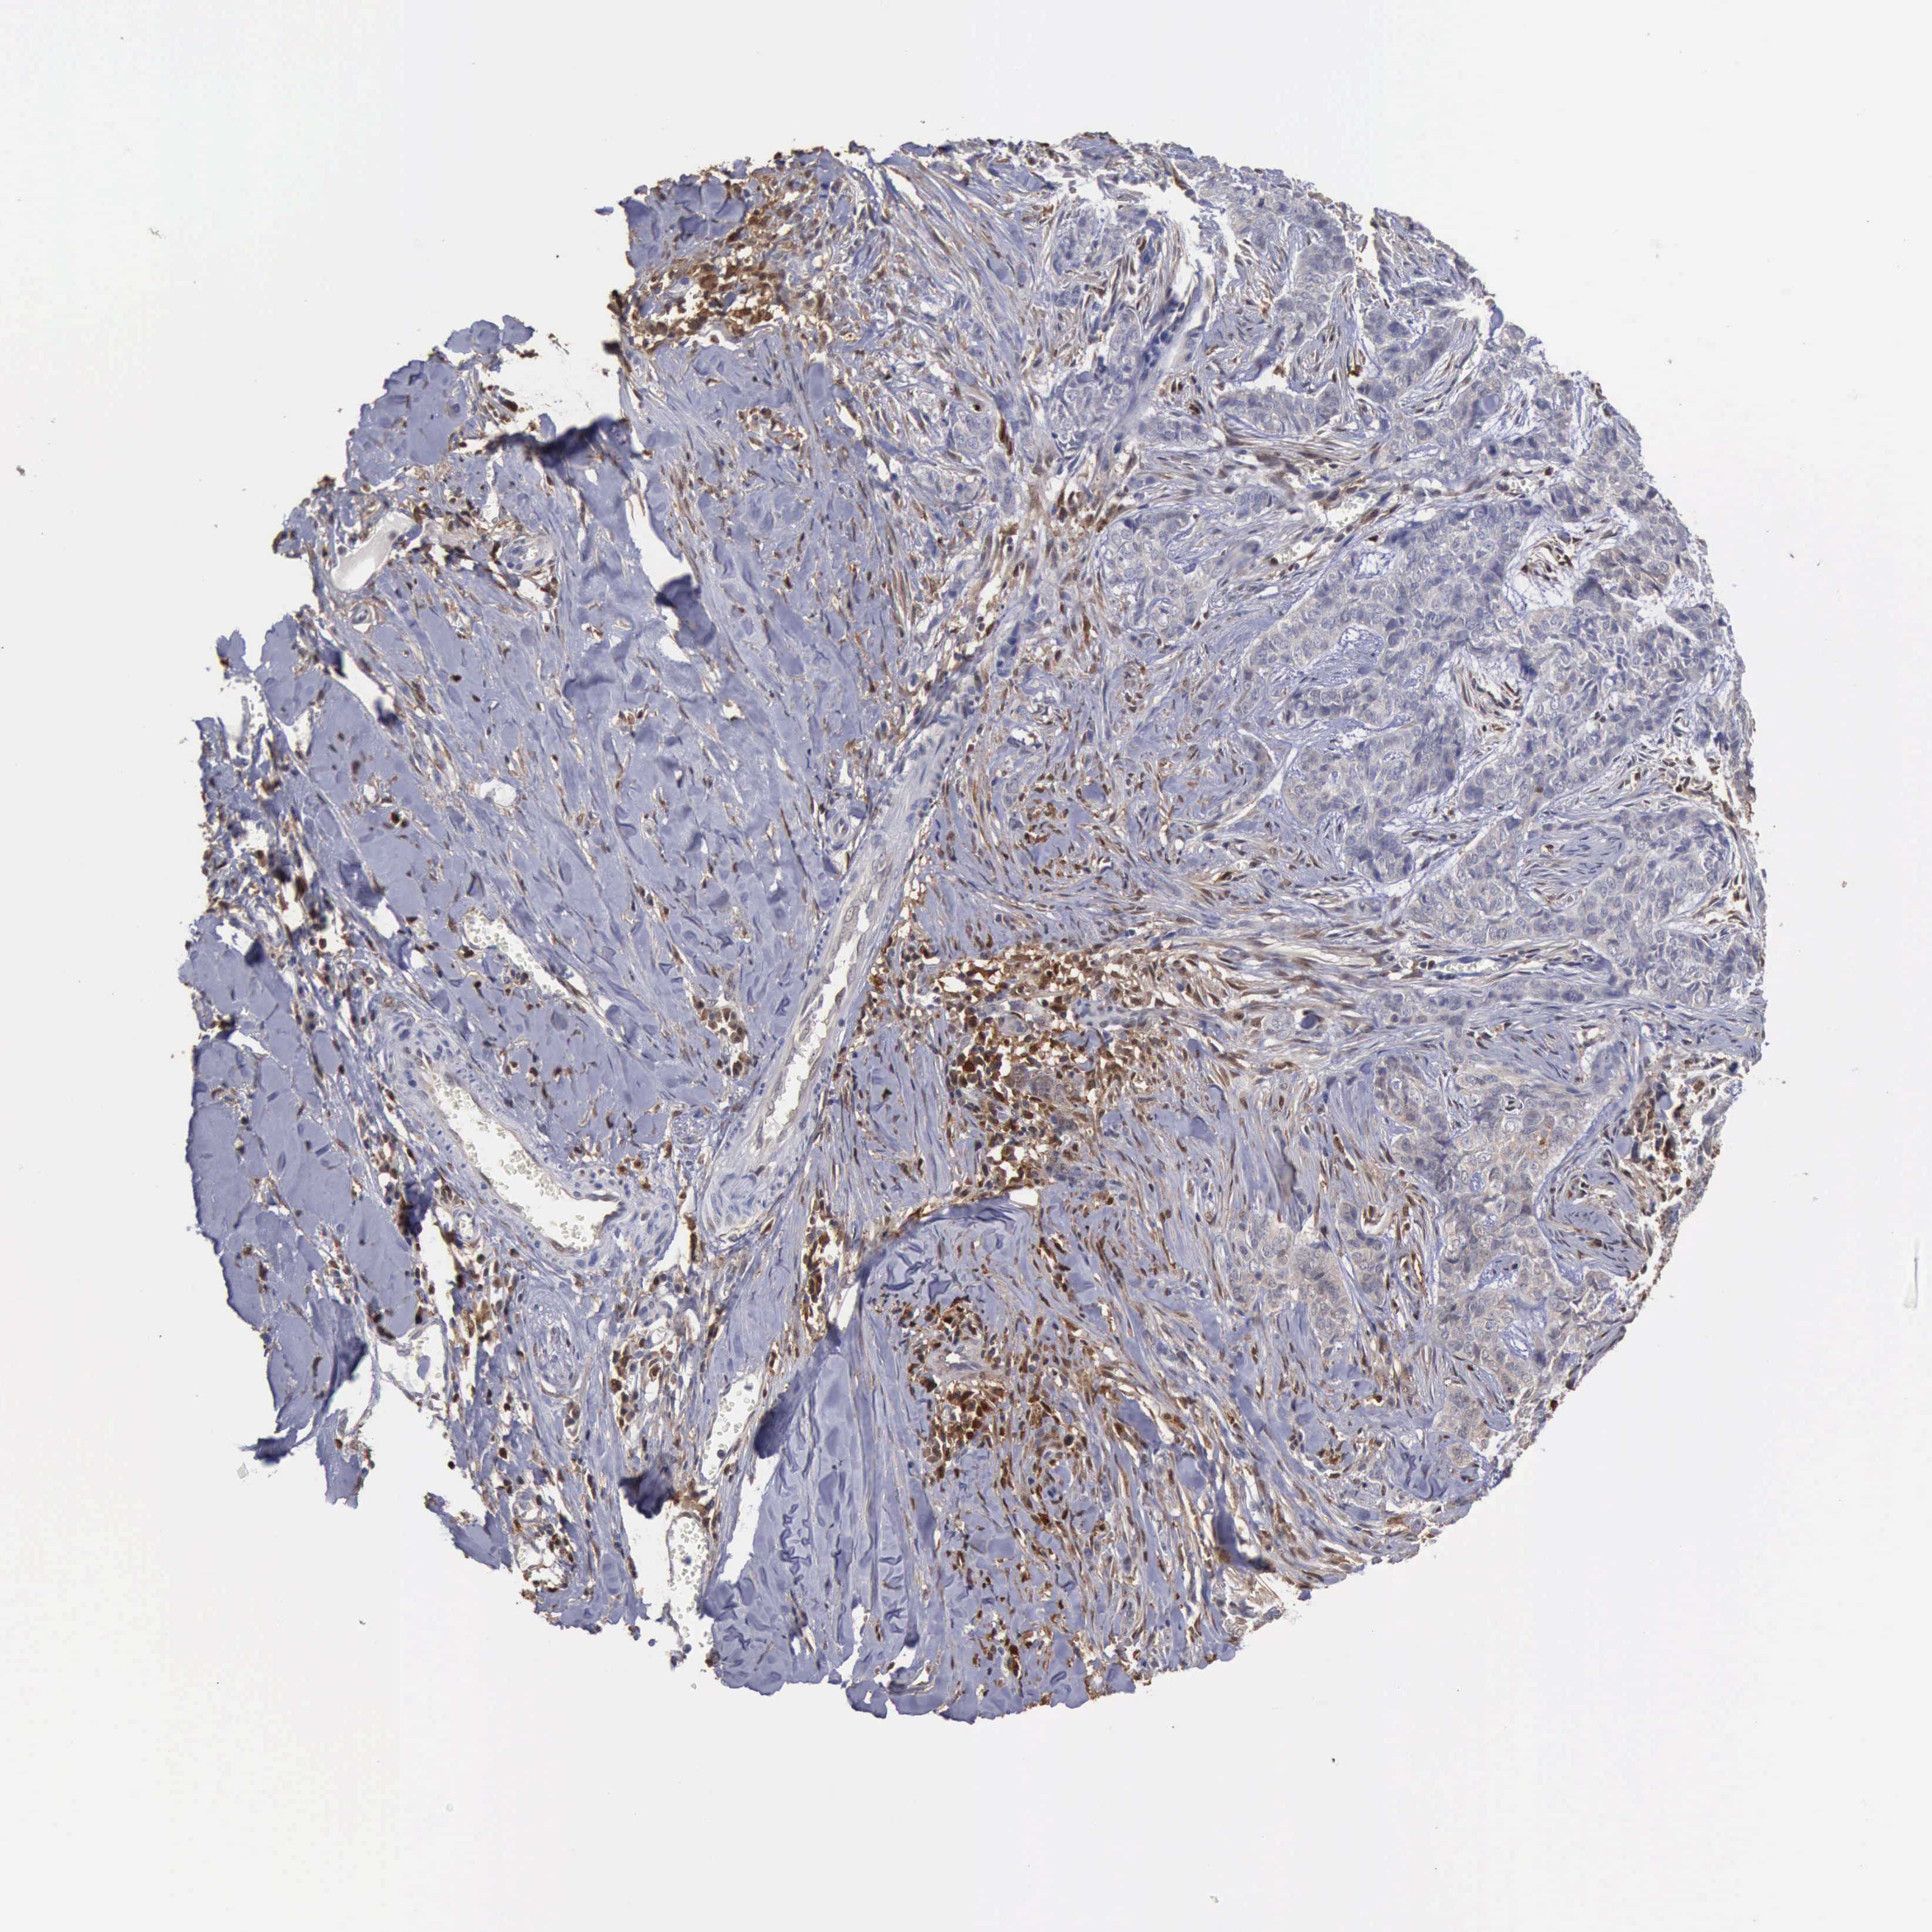

SKIN CANCER - Protein expressioni

A mouse-over function shows sample information and annotation data. Click on an image to view it in a full screen mode. Samples can be filtered based on level of antibody staining by selecting one or several of the following categories: high, medium, low and not detected. The assay and annotation is described here.

Each image is clickable and will lead to virtual microscopy that enables deeper exploration of all samples and also displays staining intensity scores, fraction scores and subcellular localization as well as patient and tissue information for each sample.

Antibody HPA000931

Staining

High

Medium

Low

Not detected

Intensity

Strong

Moderate

Weak

Negative

Quantity

>75%

75%-25%

<25%

None

Location

Nuclear

Cytoplasmic/membranous

Cytoplasmic/membranous,nuclear

Squamous cell carcinoma, NOS

Basal cell carcinoma